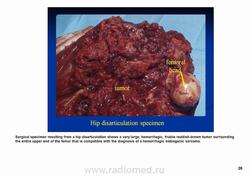

Телеангиэктатическая остеосаркома относится к остеолитическим вариантам обыкновенной интрамедуллярной остеосаркомы и содержит кистовидные сосудистые полости, разделенные тонкими костными перегородками. В некоторых случаях эта опухоль симулирует аневризматичесую костную кисту. Частота такого варианта составляет 0,4—12 % от общего числа остеосарком. Патологический перелом к моменту диагностики встречается более чем у 25 % больных, тогда как лиц с обыкновенной остеосаркомой — не более чем 5 %. У пациентов старшей возрастной группы, а также лиц с поражением костей осевого скелета развитие телеангиэктатической остеосаркомы происходит на фоне болезни Педжета. Макроскопически эта опухоль имеет вид то крупного сгустка крови или некротической массы, то многокамерной кисты, содержащей жидкую кровь, как это бывает в аневризматической костной кисте.

Макроскопически ткань геморрагична; редко встречаются плотные «мясистые» поля.